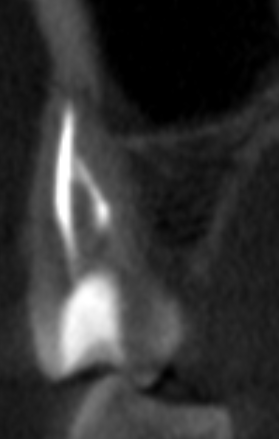

Вчера сделал КТ и стало понятно, что в двух корнях выведен материал за верхушку что аж у корней шляпки появились, а другой корень недопломбирован до конца на несколько миллиметров. Я читал что материалы выводить за апекс в принципе нельзя и это чревато, неужели пульсация над бровью и в области виска связана с этим? Он же и после удаления зуба там останется, как я понял. Где этот материал находится судя по снимкам? Не может ли он как-то влиять на тройничный нерв (не разбираюсь с этим)?

Screenshot_4.png.5e7921a698b28cc04edfe2a9ef1ab7c6.pngScreenshot_5.png.3786d148a30936dc0c8bb6475d7b25c7.pngScreenshot_6.png.cac5adb8499290207c4c9a6019795985.pngScreenshot_7.png.c63e3bf191b149a107f5b4664370a2df.png

Или в недопломбированном канале мог остаться нерв и давать такие симптомы?

Подскажите, пожалуйста, что тут можно сделать и насколько опасен этот выведенный материал. Вроде бы пломбировали Thermafil AH+.